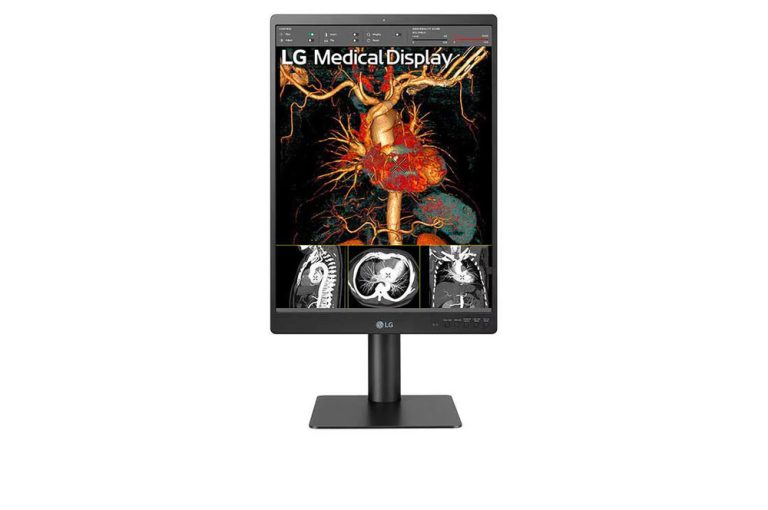

LG 21HQ513D-S – 21″ 3MP Diagnostic Medical Monitor

SKU:

21HQ513D-S

LG 21HQ613D-B – 21″ 5MP Diagnostic Medical Monitor

SKU:

21HQ613D-B

LG 24HR513C-B – 24″ 2MP Diagnostic Medical Monitor

SKU:

24HR513C-B